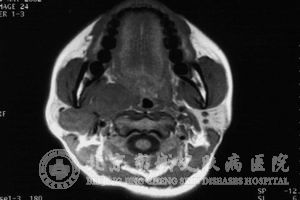

1.颅内肿瘤:听神经瘤是其中较常见的症状之一,神经性纤维瘤病Ⅱ型的主要特征是双侧神经瘤,另外患者还可能会发生脑膜脊膜瘤、多发性脑膜瘤、神经胶质瘤、脑室管膜瘤、脑膜膨出和脑积水、脊神经后根神经鞘瘤等,视神经、三叉神经及后组脑神经都可能出现症状,还有少数患者可能会出现智力减退、记忆障碍、癫痫发作等症状;

2. 椎管内肿瘤:在神经性纤维瘤病患者的脊髓平面均可能发生单个或多个的神经纤维瘤、脊膜瘤,能够合并发生脊柱畸形、脊髓膨胀突出、脊髓空洞症等;